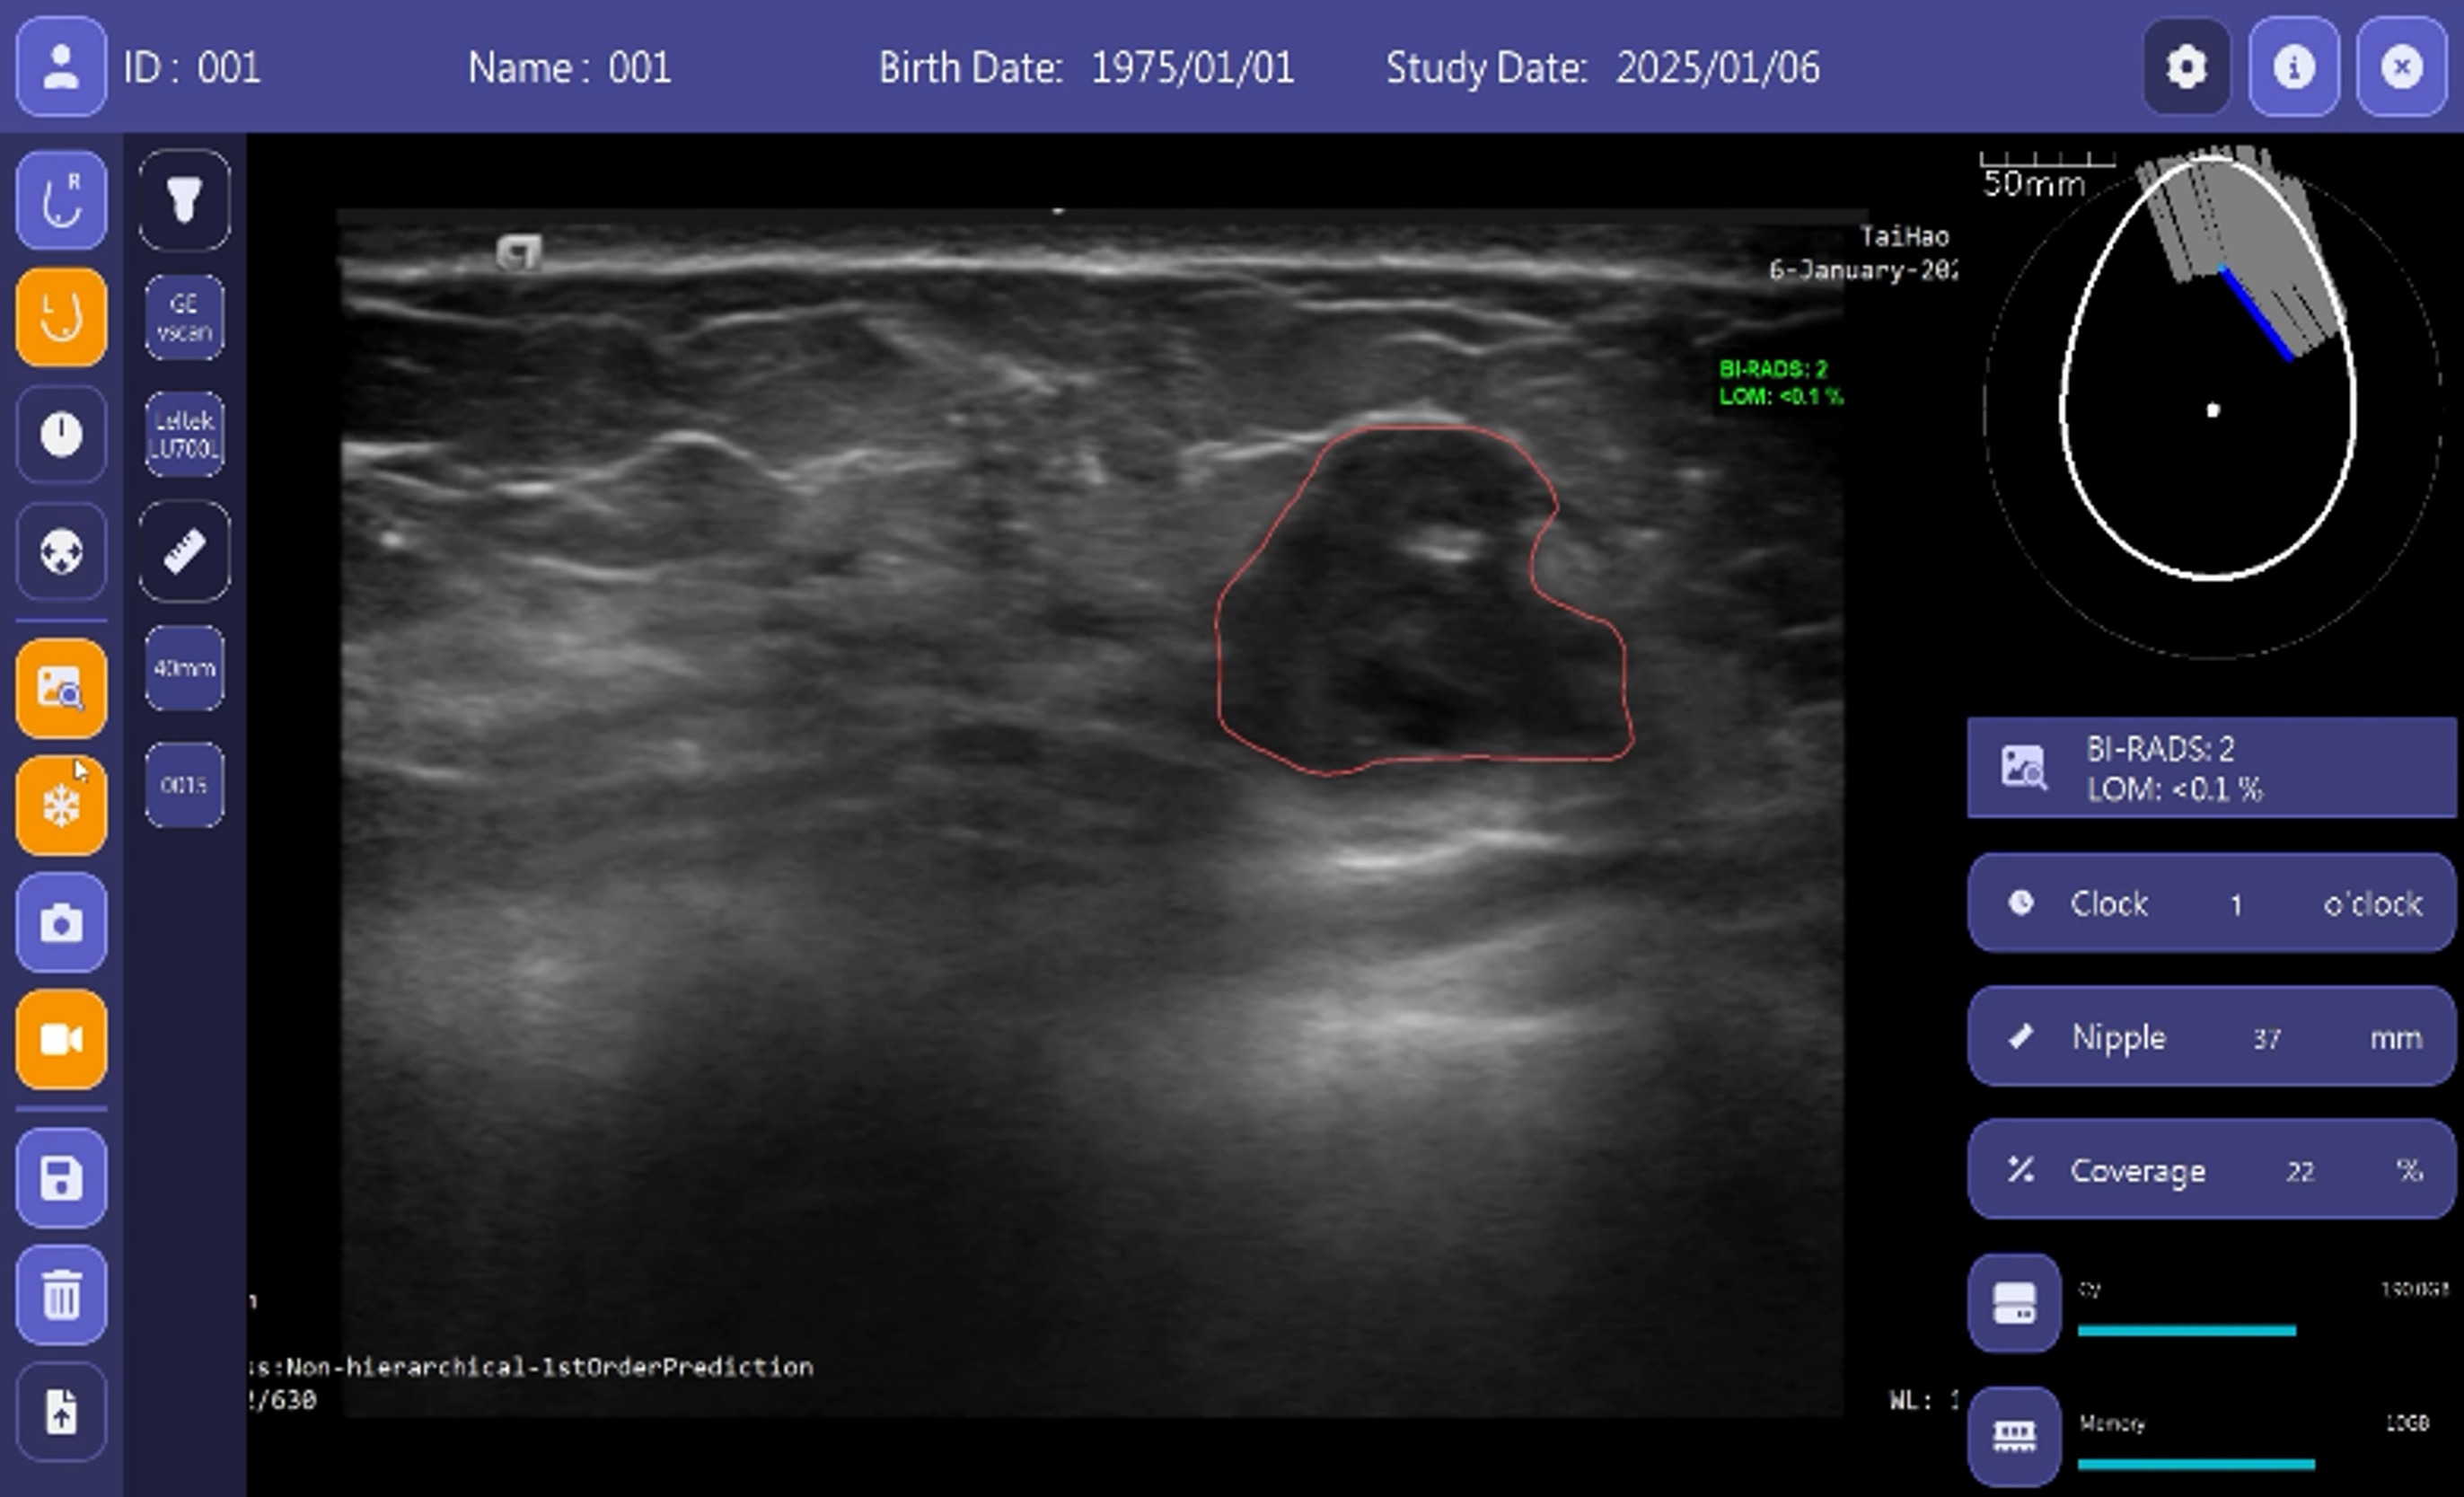

「手持式超音波全乳智慧掃描檢視系統」可適用市面上現有超音波系統,除了記錄影像外,同步記錄掃描方位、掃描角度以及掃描覆蓋率資訊,協助操作人員即時觀看乳房掃描的完整度,避免遺漏而影響診斷,在掃描的過程中提供病灶警示功能供掃描者參考,當有任何懷疑時,AI可提供該病灶的輪廓、尺寸等資訊供參考。

太豪生醫的乳房超音波AI智能檢查方案以「手持式超音波全乳智慧掃描檢視系統」與「超音波乳房腫瘤電腦輔助決策支援系統BU-CAD™ DS」為核心,該技術針對乳癌早期篩檢,提供快速精準的影像分析,醫師判讀準確率提升4.5%,閱片時間縮減39%,顯著降低誤診風險並優化醫療效率。產品已獲台灣TFDA、美國FDA、日本PMDA及韓國MFDS認證。